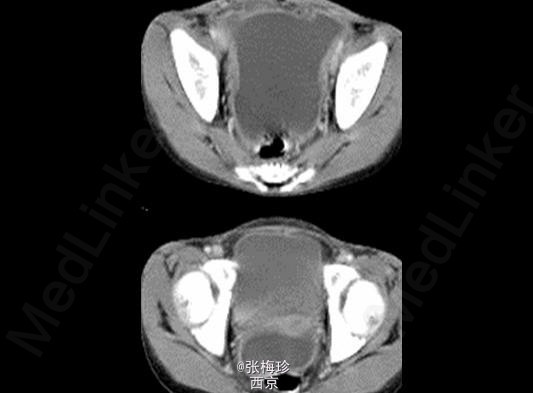

临床一例结核性腹膜炎

结核性腹膜炎

女,9岁,上腹闷痛伴腹水1年余前来就诊

查体:消瘦面容,腹膨隆,上腹部有轻压痛,无明显反跳痛,大小肿物,移动差

结核性腹膜炎 处理:药物治疗,足量、联合为治疗原则